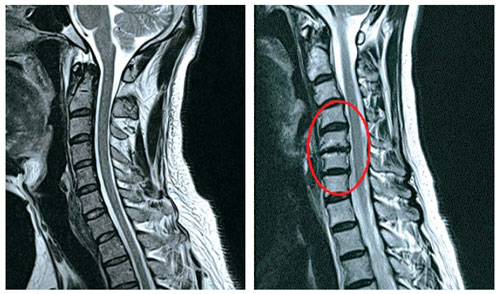

목 디스크 증상 총 정리 중 원인이고요. 한방 의학정보에 의하면 목 디스크는 목 뼈 사이 추간판이 파열됐거나 탈출되어 경추 신경의 자극, 압박으로 인하여 목, 어깨, 등, 팔 등 통증과 신경학적 증상이 있는 질환이예요.

경추는 제일 위쪽 목에 있는 7개의 뼈이라고 합니다. 경추는 운동성이 크므로 경추의 추간판은 압력에 의해 탈출되어 척수, 신경근을 억압되게 된다 하였습니다.

디스크로 인해 척수가 눌리면 팔에 힘이 빠지게 되고 눌린 정도에 따라 마비가 될 수 있다고 합니다.